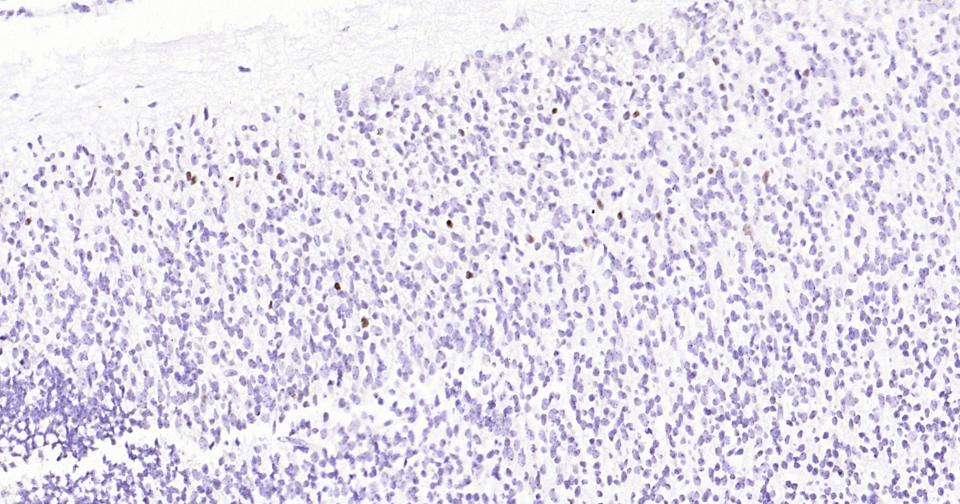

Paraformaldehyde-fixed, paraffin embedded Mouse Embryo; Antigen retrieval by boiling in sodium citrate buffer (pH6.0) for 15 min; Antibody incubation with WT1 Monoclonal Antibody, Unconjugated(bsm-60926R) at 1:200 overnight at 4°C, followed by conjugation to the SP Kit (Rabbit, SP-0023)and DAB (C-0010) staining.